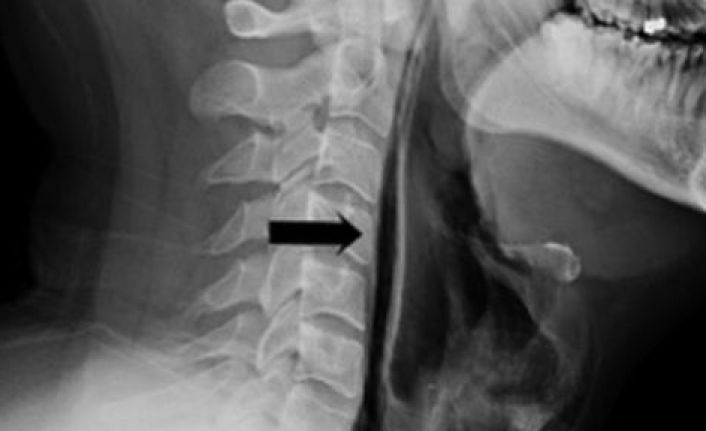

Çekilen röntgen sonucu, nefes borusundan kaçan havanın boğazındaki yumuşak doku ve boyuna gittiği anlaşıldı. Hasta, dokular iyileşene dek yedi gün boyunca bir tüple beslenmek zorunda kaldı ve daha sonra taburcu edildi. Hastanın tedavi edildiği Leiceste’daki hastanenin Kulak Burun Boğaz bölümündeki doktorlar ise, “Burun ve ağzı kapatarak hapşırığı durdurmak tehlikeli bir şey ve kesinlikle yapılmamalı” diyor. (BBC Türkçe)